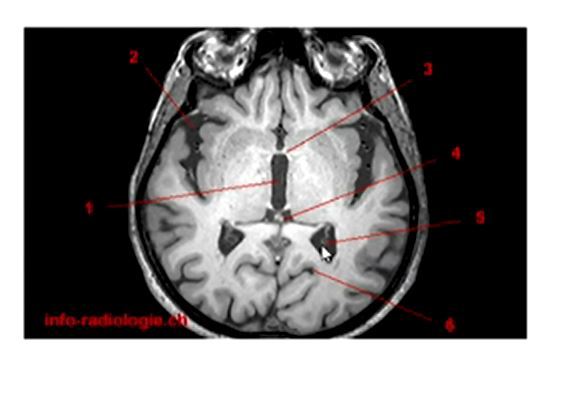

Label 1 and 5

1) Third ventricle

5) Posterior horn of lateral ventricles